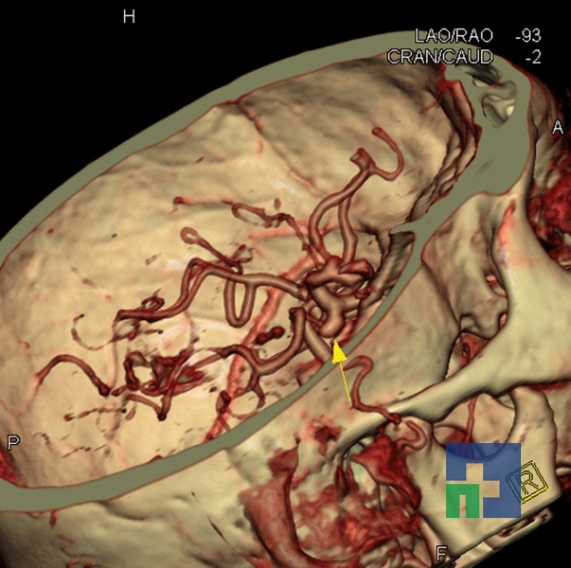

Examinare de rutină cerebrală, nativ și cu substanță de contrast (SDC) pentru diagnosticul:

- Accidentelor vasculare cerebrale ischemice sau hemoragice